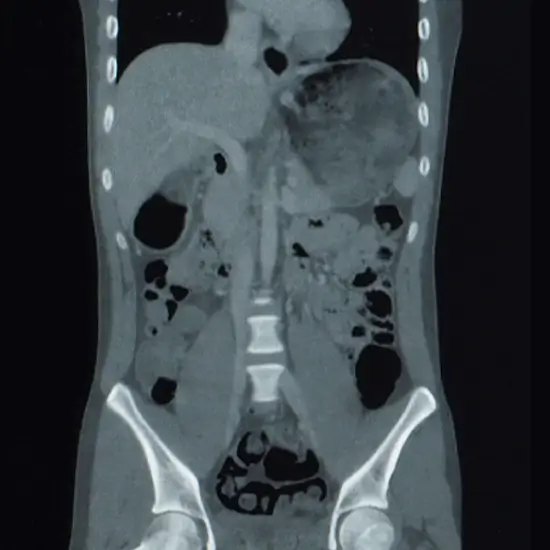

CECT upper and lower abdomen is the best method for evaluation of abdominal pain, suspected cancer, kidney diseases or gallbladder stones and any kind of infections and swelling. It is also used to detect the biliary system (liver, pancreas, gall bladder etc).

A diagnostic imaging technique called CECT (Contrast enhanced computed tomography) is used to produce finely detailed images of the blood vessels, soft tissues, bones, and internal organs. Intravenous contrast dye is injected into the body during this test to help provide a clear picture of the blood vessels. Additionally, it aids in the diagnosis of biliary system issues (liver, pancreas, gallbladder, etc.).

When it comes to identifying infections, kidney or gall bladder stones, abdominal pain, and possible cancer, CECT scanning is frequently regarded as the most effective technique to detect the problems in the abdomen.

The CECT upper &lower abdominal scan shows the biliary system including the liver, gallbladder, pancreas, stomach, intestines, urinary system, etc. When identification and examination of the internal organs of the abdomen are indicated, the CECT scanning is regarded to be the most effective technique.